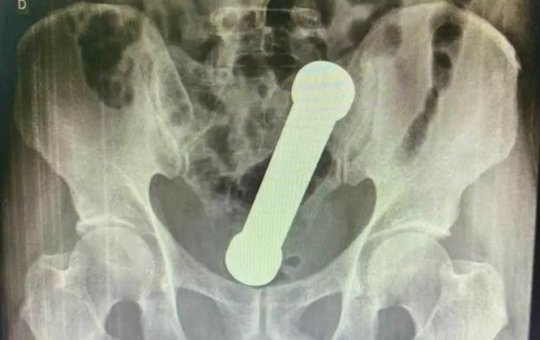

Médicos removem haltere de 2kg do ânus de homem; caso aconteceu em Manaus

Paciente de 54 anos foi a unidade de saúde com reclamações de cólica, náuseas e vômitos